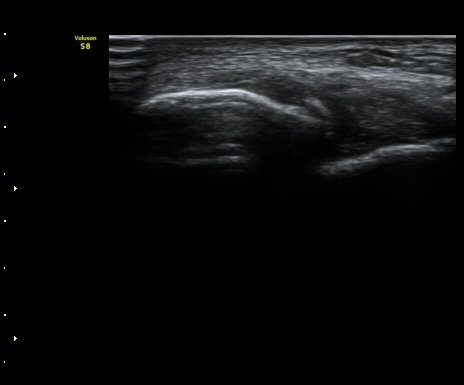

Àü¹æ°Å°ñºñ°ñÀδë Á¾´Ü¸é°Ë»ç¿¡¼­ ¹Ì¼¼ÇÑ ºñ°ñ¿¡¼­ ¹Ú¸®µÈ ¹Ì¼¼ °ñÆí°ú

ÀδëÀÇ Àú¿¡ÄÚ ºÎÁ¾ÀÌ °üÂûµÈ(±×¸² 2).